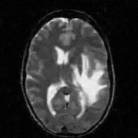

The reconstructions of a 256×256256256256\times 256 brain image from its radial samples acquired with a 40 spoke trajectory are shown in Fig. 6. The measurements are corrupted with zero mean complex Gaussian noise of standard deviation σ=18.8𝜎18.8\sigma=18.8. All methods result in loss of subtle image features since the acceleration factor and the noise level are high. We observe that the NLS scheme provides better recovery than the competing methods. The quantitative results in this setting for various MR images are shown in the bottom section of Table IV. We observe that the SNR improvement offered by NLS over the other methods are not as high as in the previous cases, mainly due to the considerable noise in the data and the high acceleration.

Refer to caption

(a) Original

(b) DLMRI,SNR=17.46

(c) TV,SNR=17.43

(d) NLS,SNR=18.46

(e) Sampling pattern

(f) DLMRI error

(g) TV error

(h) NLS error

Figure 6: Comparison of the algorithms in the presence of noise. We consider the recovery of a 256×256256256256\times 256 original MRI brain image from its radial trajectory with 40 spokes, contaminated by Gaussian noise with standard deviation σ=18.8𝜎18.8\sigma=18.8. The error images are magnified by a scale of 5 fold for the best visibility. This is a challenging case due to the high undersampling factor and high measurement noise. We observe that the NLS scheme provides the best overall reconstructions.